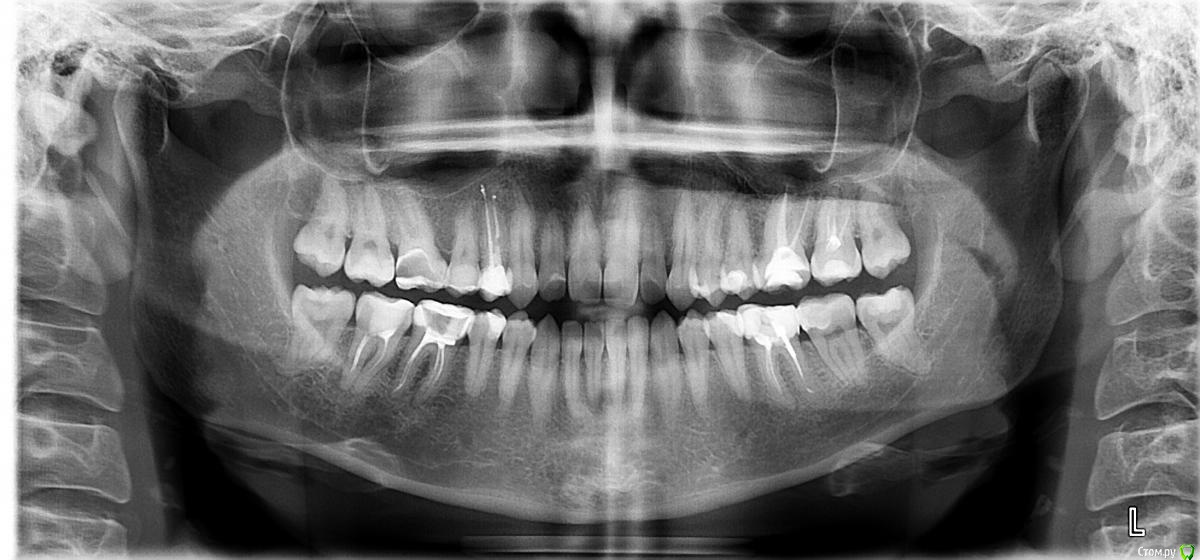

После лечения жевательных зубов на нижней и верхней челюсти начался дискомфорт в прикусе. Врач подшлифовал пломбы, начались боли в мышцах. Попробывал завысить, стало еще хуже. Через месяц начались щелчки с левой стороны, боли усиливались в районе жевательных мышц. Пробывали капы, результатов не давало. Сейчас не могу ни переживать толком еду, спать вообще не удобно. челюсть в обычном положении зафиксировать не могу, жевательных мышц совсем не чувсвую,разговаривать тоже не удобно, слюну ковтать трудно.Сильно напряжены мышцы возле носа, сзади головы и шеи, раслабить никак не могу. Начались сильные головные боли, боли в шее, в левой лопатке.  Сделали мрт шейного отдела, показало деформация шейного отдела и грыжи. Стоматологи говорят что это из-за прикуса. К кому обратиться помогите,Есть фотография до лечения, прикрепляю.

КТ даёт лишь информацию относительно костных структур сустава, а хотелось бы увидеть что там со связками, но для этого нужно МРТ. Со стороны костных структур я не увидел каких-то критических изменений, за исключением может быть ремоделирования суставных поверхностей.